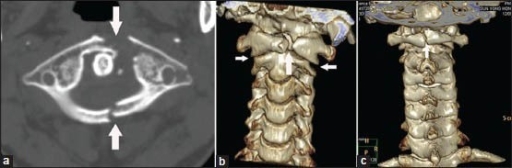

Axial and coronal CT images demonstrating a Jefferson burst fracture of C1 with bilateral anterior and posterior arch fractures. There is lateral displacement of the C1 lateral masses with a combined lateral mass displacement (LMD) of 8mm measured on open-mouth odontoid view. The transverse ligament status is concerning. This represents an unstable C1 ring fracture.